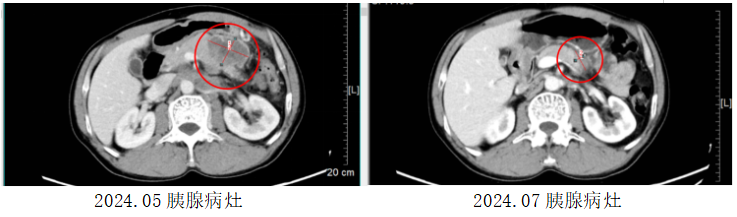

另一位患者,58岁的孙先生(化名)被诊断出胰腺神经内分泌癌伴双肺、腹腔、锁骨区、纵膈淋巴结转移。他慕名至我院肝胆胰肿瘤内科就诊。充分评估病情后,医疗团队同样为其采用了LBL-024联合依托泊苷和铂类的治疗。在2个周期的治疗后,他的肿瘤退缩65%,疗效显著。